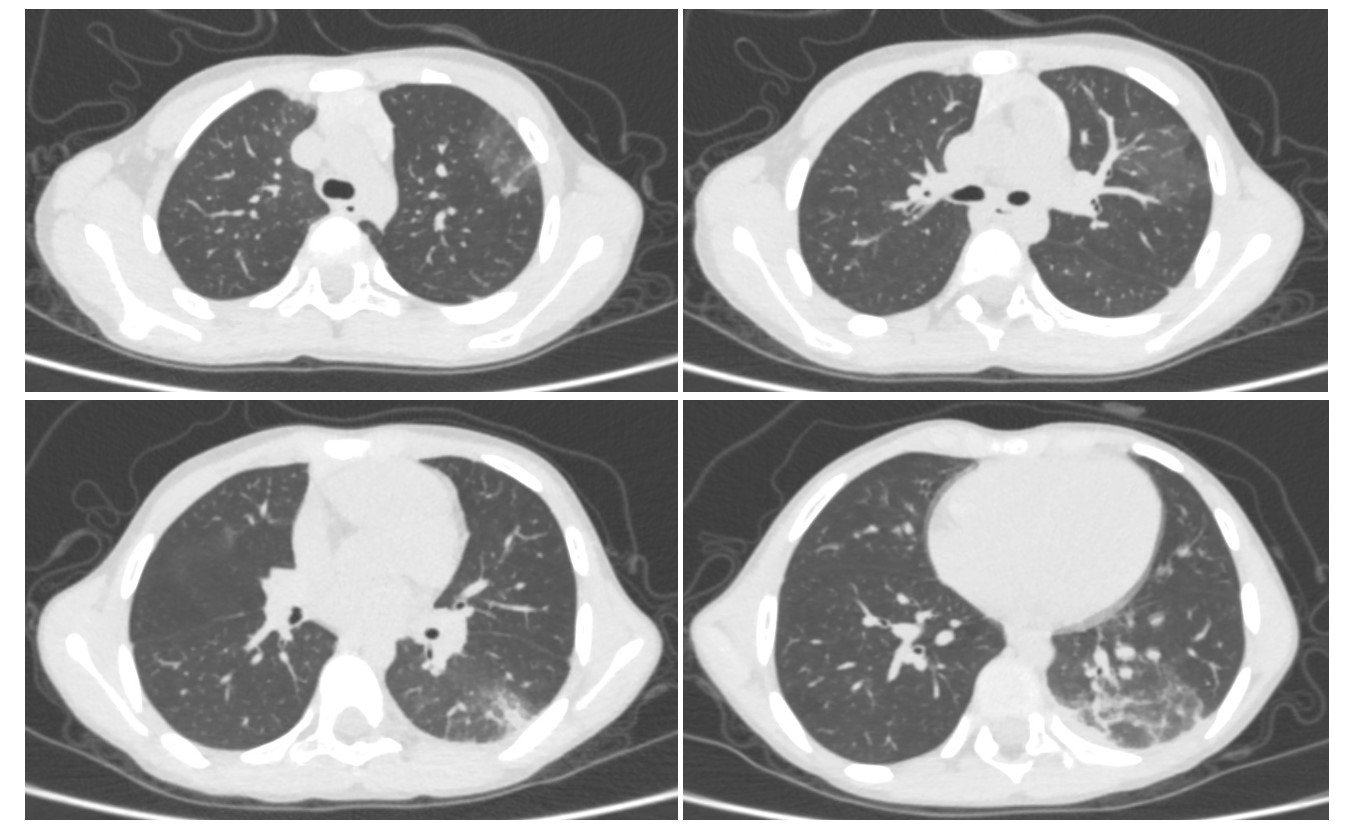

С целью оценки эффективности терапии 23.12.2024 г. ребенку было проведено также КТ органов грудной клетки: на уровне ранее выявленных зон консолидации легочной паренхимы в S3, S6, S10, S9 левого легкого при настоящем исследовании определяются участки инфильтрации с ретикулярными изменениями. В паренхиме правого легкого без очаговых и инфильтративных изменений. Трахея и крупные бронхи не изменены. Плеврального выпота не выявлено (рис.3).

Рисунок 3 - КТ-картина соответствует левосторонней полисегментарной инфильтрации с положительной динамикой в сравнении с предыдущим исследованием